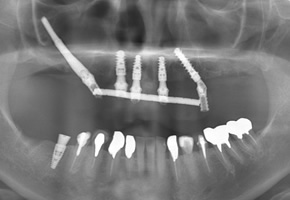

CASE07:All on 4

オールオン6(骨の状態によってはオールオン4)という技術を用いることによって、歯が1本もない患者さんでも手術をしたその日に歯が入り食事をすることが可能になります。